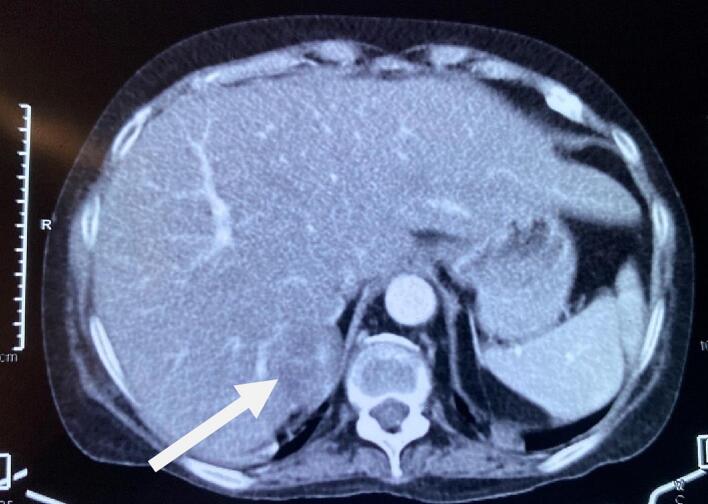

Thus, the patient was initially diagnosed and managed as a case of Cushing syndrome and Pheochromocytoma with resistant hypertension, hypokalemia, Diabetes Mellitus, and hypothyroidism. She was prescribed with Angiotensin receptor blocker, Calcium Channel Blocker, alpha-blocker (Prazosin), spironolactone, potassium chloride, and Insulin. The Computed Tomography (CT) scan of the abdomen revealed a well-defined soft tissue lesion in the right adrenal gland's lateral limb with a high washout likely lipid-poor adenoma (Fig. 1). The visualized spine had diffuse osteopenia with anterior wedging of the D8, D9, D10, D12, and L1 and L4 vertebral bodies. Contrast-enhanced CT (CECT) showed a 3.4 × 2.2 cm enhancing solid cystic lesion abutting the right adrenal gland and segment IV of the liver (Fig. 2).

Fig. 2.

CECT showing an enhancing solid cystic lesion abutting the right adrenal gland and segment IV of the liver (arrow).